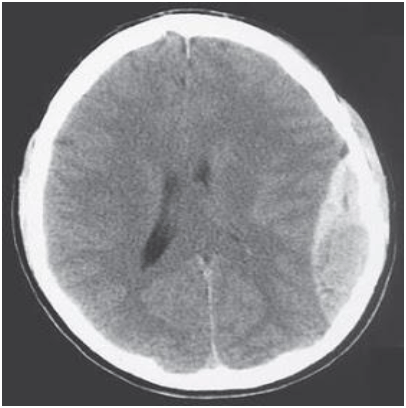

Paciente com traumatismo craniano foi atendido no pronto-socorro e foi realizado o exame a seguir. Qual o diagnóstico?

Fonte: Site Ciência Atual. Disponível em: <www.ciencia-atual.blogspot.com.br/

2009/02/serie-imagem-em-medicina-clinica-20.html>. Acesso em: 25 mar. 2013.